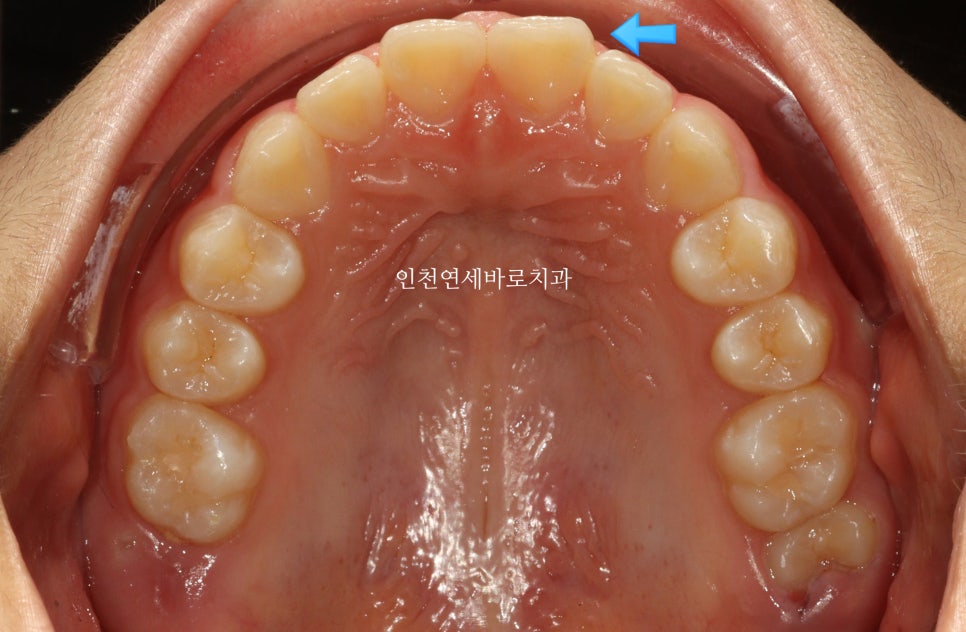

환자 초기 상태

인천연세바로치과에 온 환자아이입니다.

앞니가 튀어나와있고, 삐뚤삐뚤, 그리고

#과개교합

도 있는 아이었습니다.

14주 후 결과

거의완성되었습니다.

거의 라고 말하는 이유는 저희 의료진 눈에는 아주아주 미세한 부분이 마음에 들진 않아서요.

화살표 부분이 약간 아쉬웠기 때문입니다.